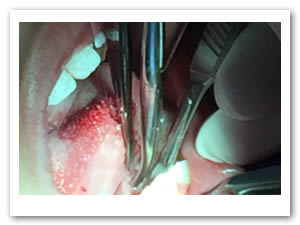

• Se realizó una incisión horizontal en la parte media del frenillo con hoja de bisturí No. 15 y mango No. 3, posteriormente se comenzó a cortar el frenillo de arriba abajo cuidando la anatomía de la región y la zona de las carúnculas sublinguales de los conductos de Wharton y Rivini. (Figuras 5 y 6).

Figuras 5 y 6. Incisión y corte del frenillo.